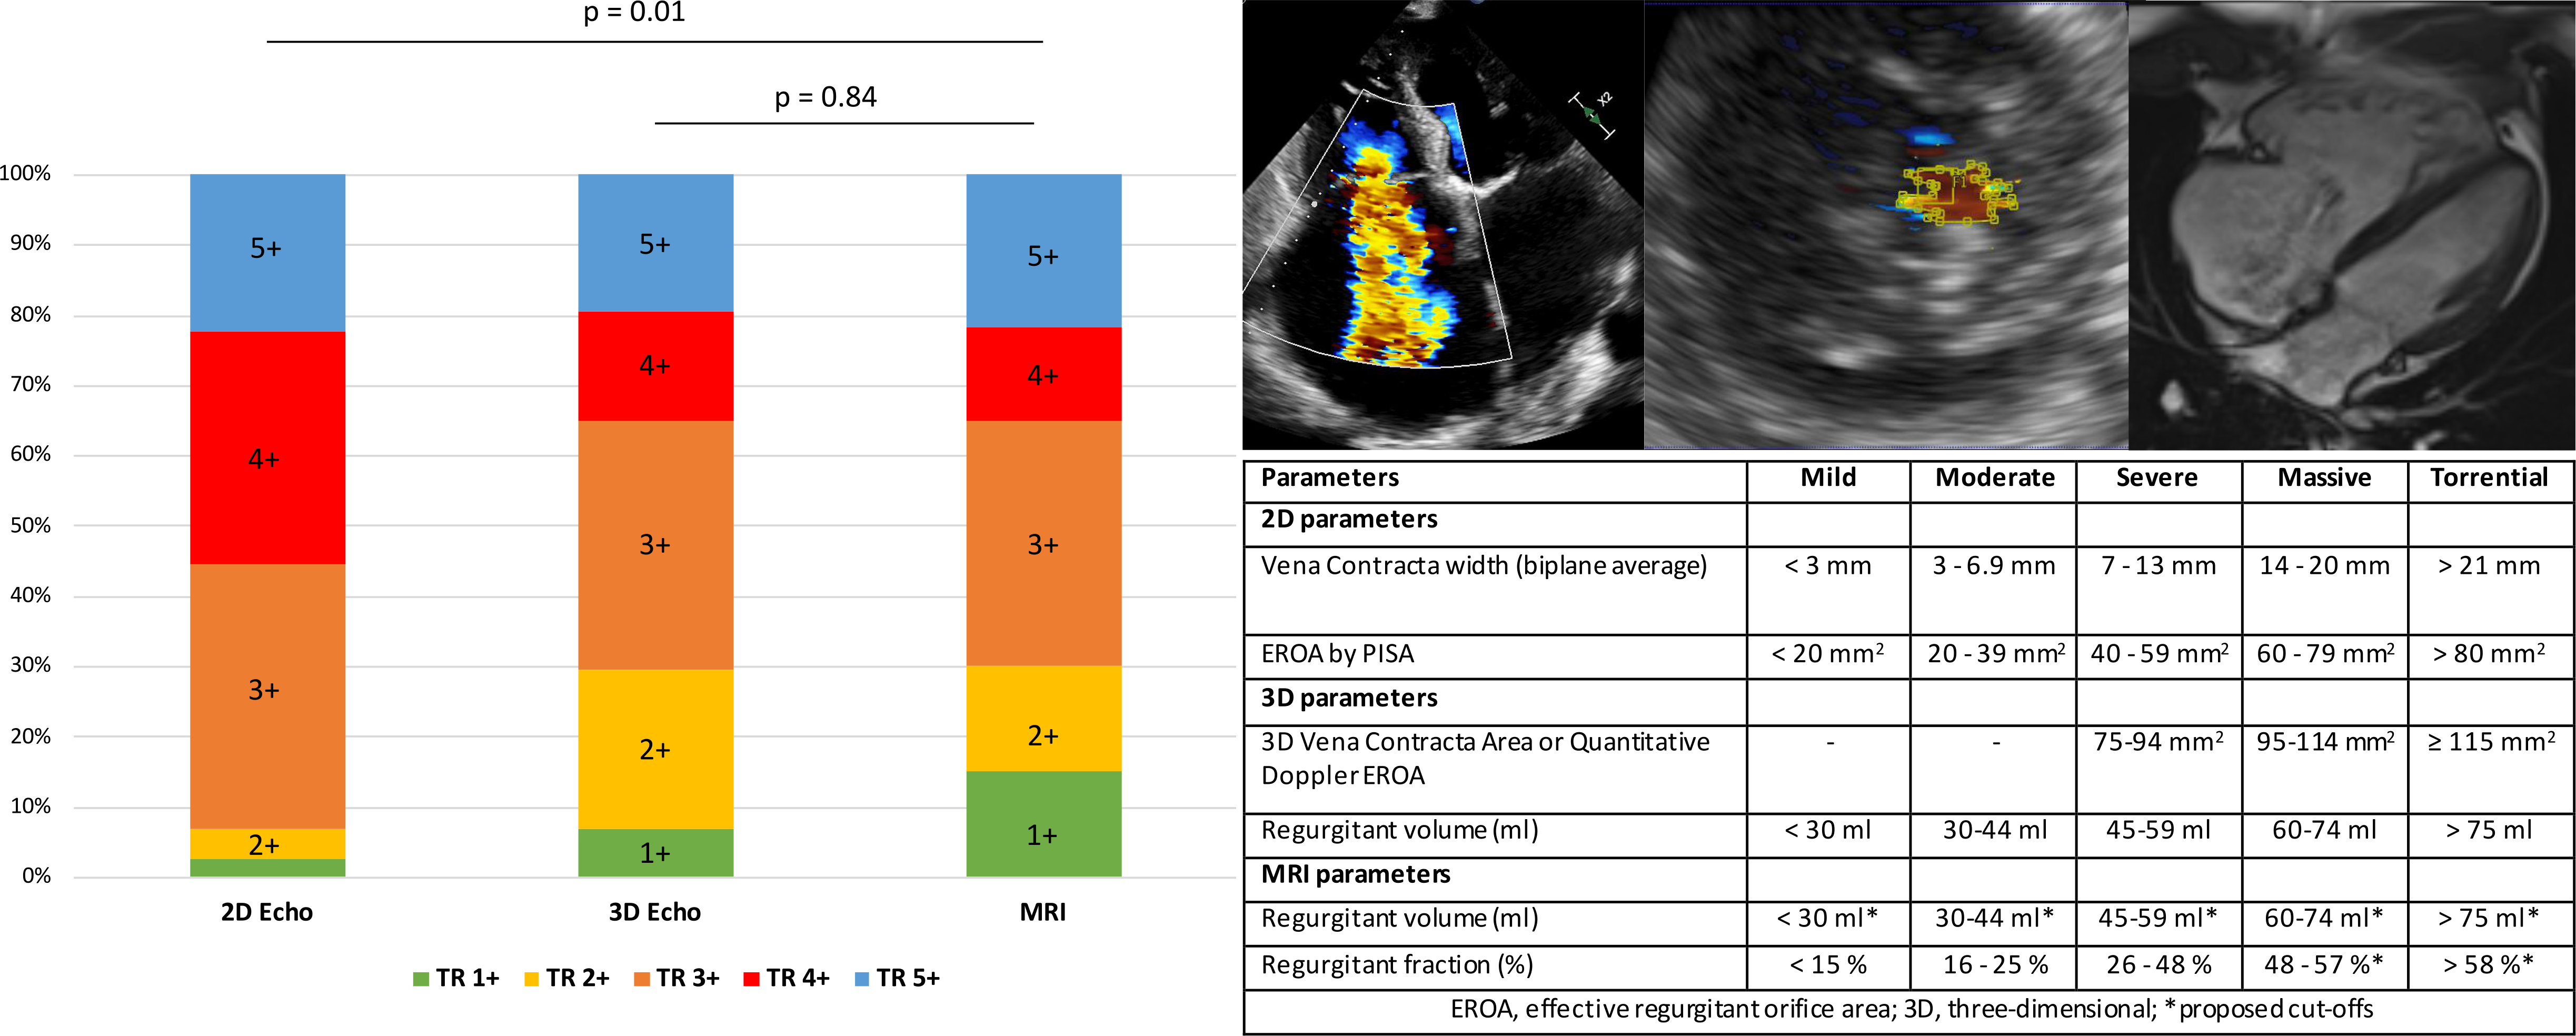

Seventy-three patients with TR were included in the study. Patients underwent 2DE, 3DE, and cardiac MRI at the University Hospital of Munich. Notably, 3DE demonstrated a superior accuracy rate, aligning with MRI findings in 85% of cases, albeit underestimating RV volumes compared to MRI. TR severity grading revealed significant discrepancies between 2DE and MRI, while 3DE demonstrated a notably better agreement with MRI. Additionally, 3DE showed comparable results in measuring RV function (3DE vs. MRI: p=0.25). Importantly, we extended the echocardiographic 5-class grading scheme to MRI, providing a comprehensive framework for TR assessment across modalities.

This research underscores the clinical utility of 3DE as a reliable method for assessing RV function and TR severity, potentially serving as a promising alternative to MRI. Accurate TR grading plays a pivotal role in guiding intervention decisions. Multimodality imaging, including MRI, is recommended for orthotopic transcatheter tricuspid valve repair and replacement therapies to guarantee the most accurate assessment of TR severity and RV remodeling. Accurate TR grading, across various imaging modalities, is essential to prevent both under- and overtreatment and to optimize patient care.